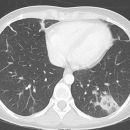

Morbus Wegener